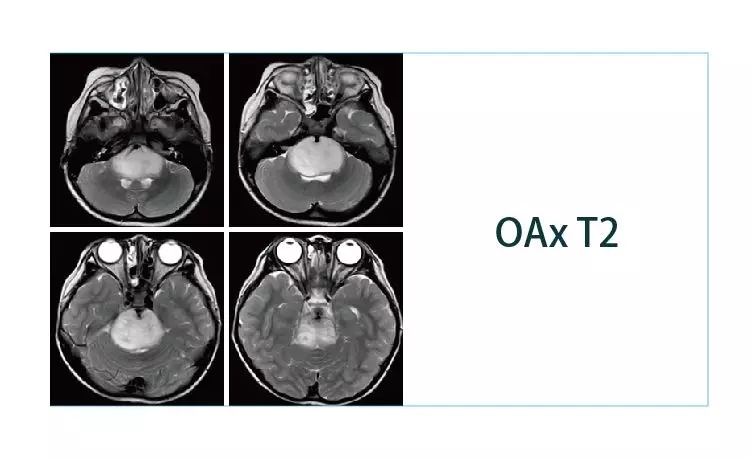

【朗润影像档案】20190329磁共振影像病例结果讨论